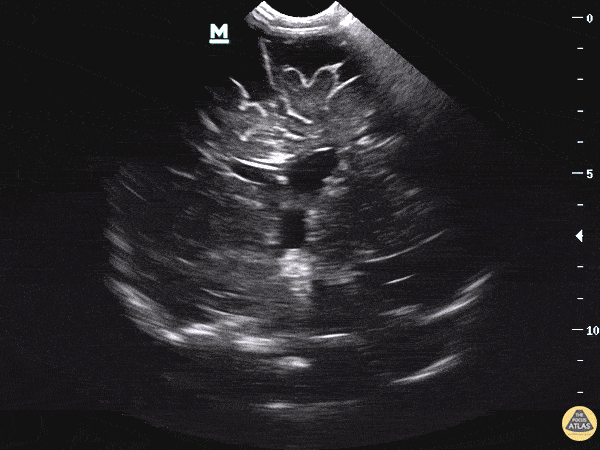

Pediatrics - Obstructive Hydrocephalus

WCUME 2017 winner for "Novel Indication" - See our blog post for a deep dive on this topic! 7 month old being followed by PCP for increasing head circumference, scheduled for outpatient MRI next week. Mother found patient was becoming somnolent with a full anterior fontanelle and brought the baby to the ER. POCUS performed immediately revealed unequal ventricle size, L>R, at which time neurosurgery was consulted, later CT, MRI performed as inpatient confirming obstructive hydrocephalus. If you were in a community ER and CT will take a while, should you just POCUS first? How well can this see blood? Masses? Dr. Sathya Subramaniam - Childrens Hospital of Philadelphia Pediatric, EM Ultrasound